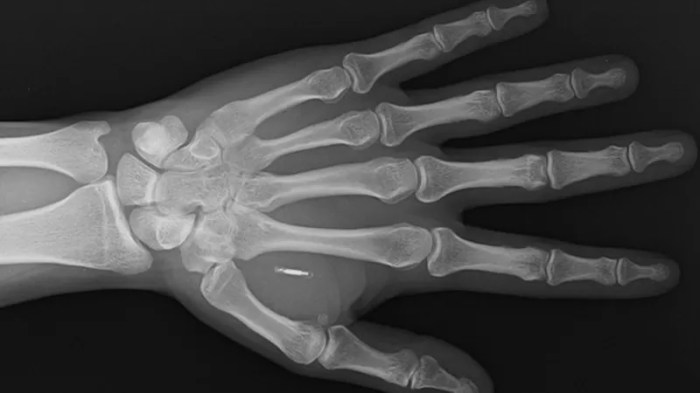

صورة بالأشعة توضح الشريحة مزروعة في اليد اليسرى لأحد الأشخاص، وهي توضع باستخدام مخدر موضعي